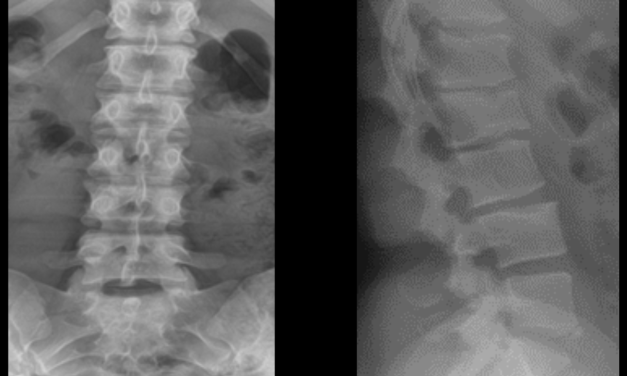

Atypical Proximal Femoral Fracture: An Important Diagnostic Consideration for Patients With Hip, Groin, Or Thigh Pain

Explore the intricacies of hip pain in individuals taking bisphosphonates, uncovering the lesser-known atypical proximal femoral fracture as a potential cause. Dive into the article for a deeper understanding!